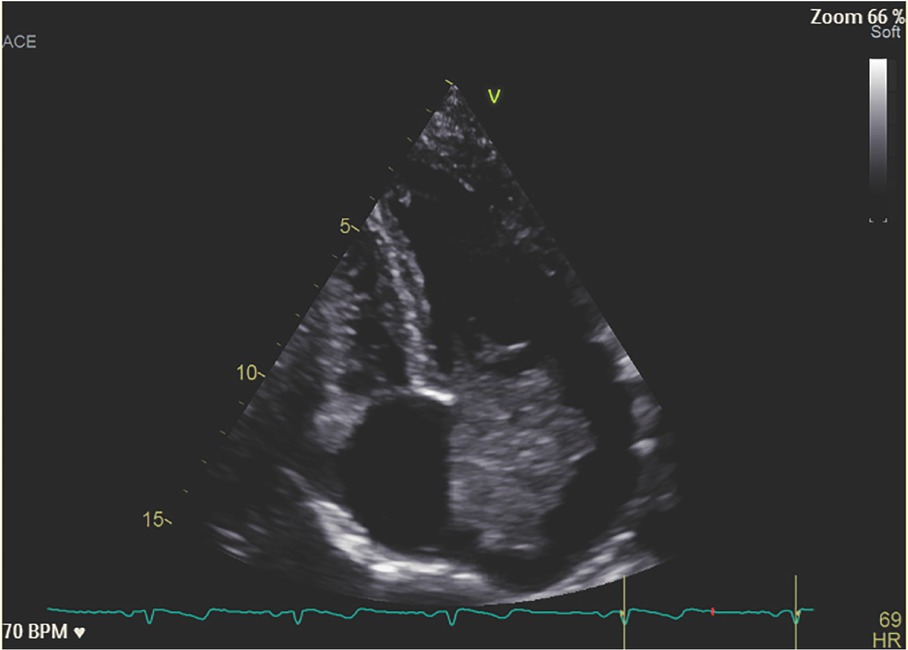

The mass was 4223 mm in diameter compatible with an AM (Figure 2). The patient was operated with the mass removed. After surgery, the patient reported a complete resolution of the articular and cutaneous symptoms and methylprednisolone and MTX were withdrawn.

Figure 2 Echocardiographic image of the AM occupying almost all the left atrium and mitral valve. AM, atrial myxoma.

Echocardiographic image of the AM occupying almost all the left atrium and mitral valve. AM, atrial myxoma.